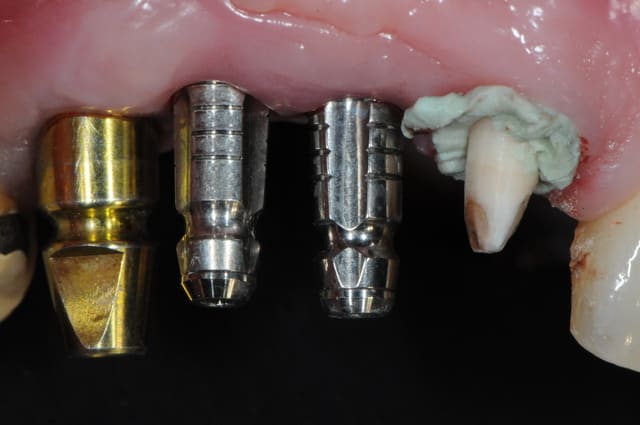

pose implants

cicatrisation gingivale

mise à jour et aménagement tissulaire type Palacci

modification des collets et des bords libres

prise empreinte

piliers

couronnes...